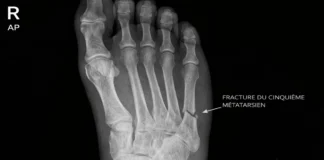

Fracture

Fractures Métatarsiennes : Identifier et Traiter les Blessures du Pied

7 mai 2025